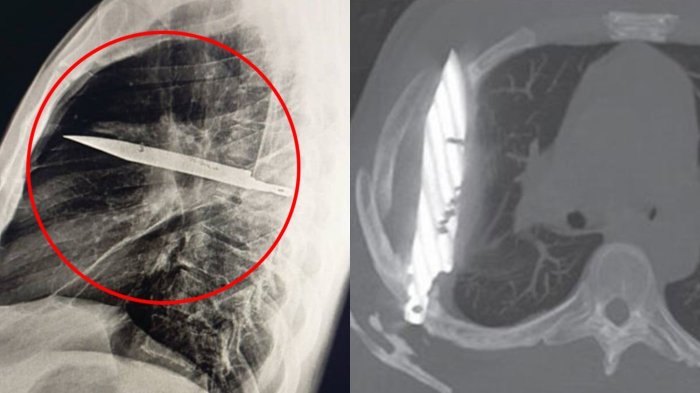

Luego del homicidio frustrado, el hombre trató de atentar contra su vida, pero no lo logró. Debido a lo violento del hecho y la gravedad de las heridas, al lugar tuvo que acudir servicios de urgencia, Carabineros y Seguridad Ciudadana.